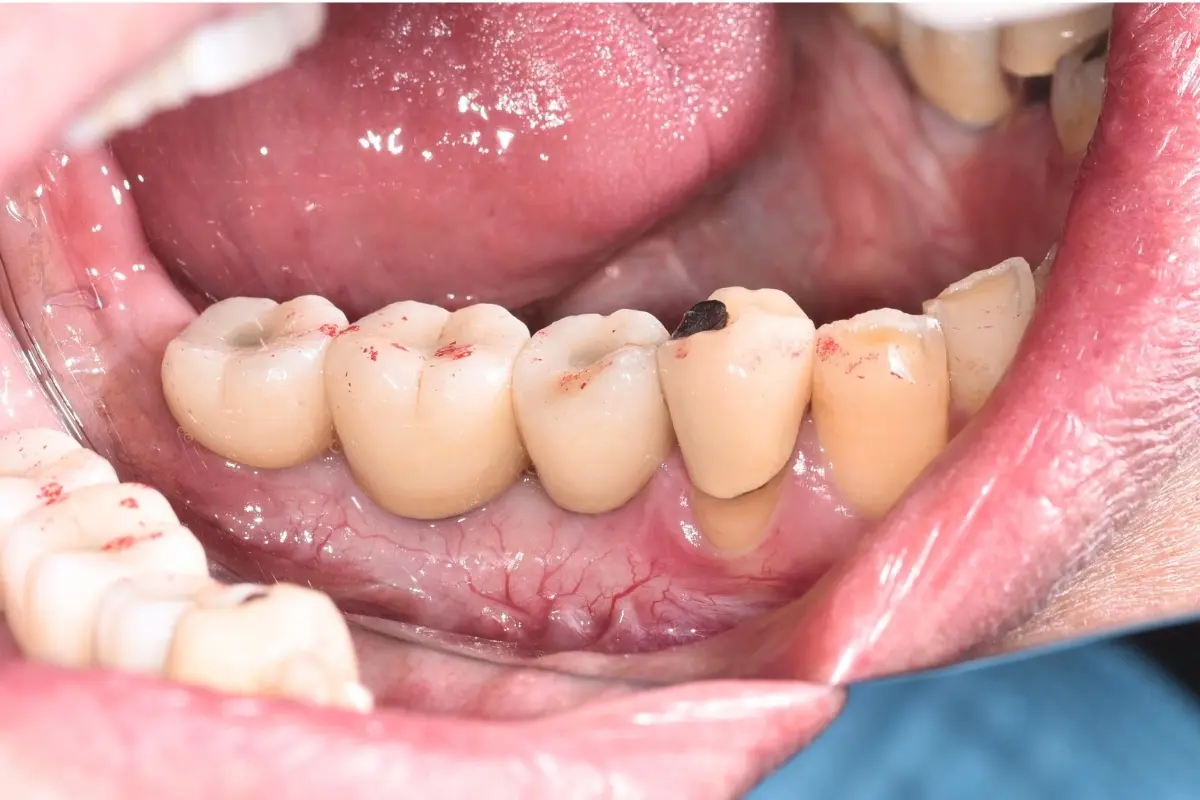

• 自體牙移植術前

自體牙移植術後

口腔外科/自體牙移植

主治醫師

• 林明志

治療時間

單次療程

主訴

矯正治療前發現牙齒嚴重蛀牙,無法保留